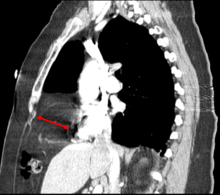

This rare anterior defect of the diaphragm is variably referred to as Morgagni, retrosternal, or parasternal hernia. Accounting for approximately 2% of all CDH cases, it is characterized by herniation through the foramina of Morgagni which are located immediately adjacent and posterior to the xiphoid process of the sternum.[3]